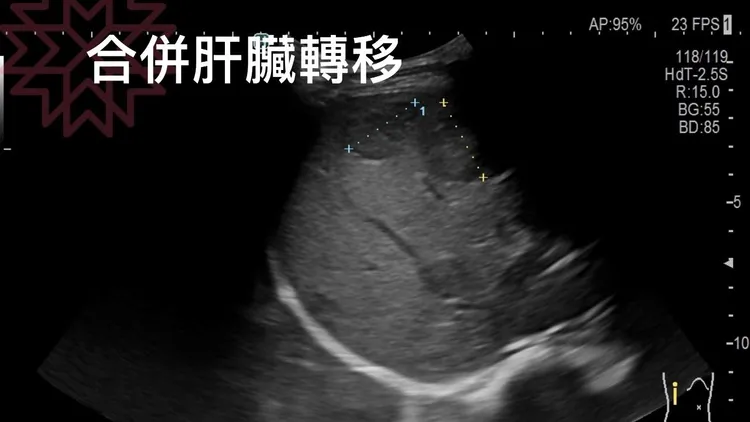

惡性肉瘤合併肝臟轉移。翻攝自胰臟醫師 林相宏 禾馨民權內科診所臉書

林相宏表示,他聽完病史後請患者躺下,「還沒摸,上腹部一看就有一坨東西鼓起來,觸診一摸是一顆很硬而且不規則的腫瘤,超音波一照不得了,肚子裡面竟有一顆13公分的腫瘤」。林相宏解釋,因為頂到胃部,患者才會腹痛吃不下,結果是惡性肉瘤合併肝臟轉移。